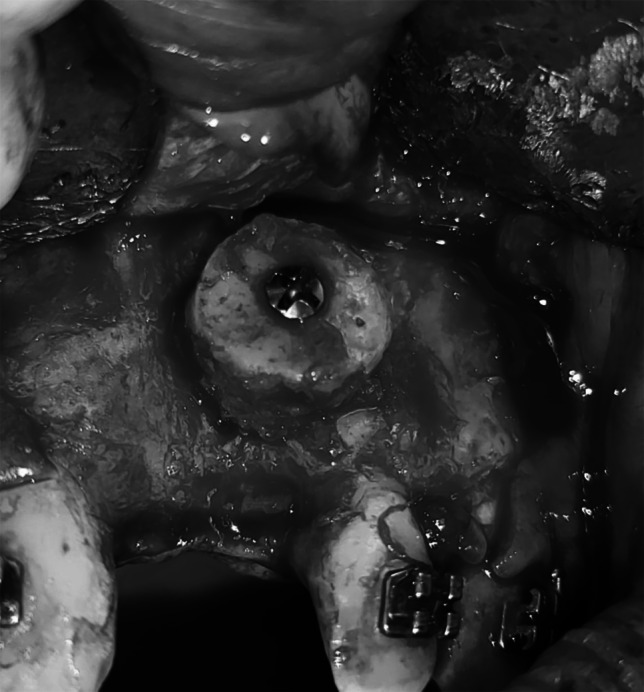

有许多因素可以影响下颌缺陷的矫正和特定移植材料的成功,包括上颌和下颌骨的组织学和密度以及移植材料本身。本研究比较了使用混合可注射富血小板纤维蛋白(i-PRF)或异种移植物的下颌联合嵌骨移植增强前上颌水平牙槽嵴的临床结果。将12例成人上颌牙槽嵴水平缺损患者随机分为两组,每组6例。I组采用下颌联合嵌骨移植物混合I - prf, II组采用下颌联合嵌骨移植物混合异种移植物(InterOss有机松质颗粒)。术前和随访6个月时采用CBCT扫描测量牙槽嵴宽度和骨密度。两组牙槽嵴宽度和骨密度均有改善。6个月后测量骨宽度和骨密度的增加,II组显著大于I组(p = 0.040)。水平牙槽嵴增强术采用嵌板下巴移植物结合异种移植物是成功的,并提供了足够的骨数量和质量。

There are numerous factors that can impact both the correction of jaw deficiencies and the success of a particular grafting material, including the histology and density of both the maxillary and mandibular bones and the grafting material itself. This study compares the clinical outcomes of grafted augmentations of the horizontal alveolar ridge of the anterior maxilla using mandibular symphysis onlay bone that was admixed with either injectable platelet-rich fibrin (i-PRF) or xenografts. Twelve adult patients with horizontal maxillary alveolar ridge deficiency were randomly divided into two groups of six patients each. Group I received mandibular symphysis onlay bone grafts mixed with i-PRF, while Group II received mandibular symphysis onlay bone grafts admixed with xenografts (InterOss anorganic cancellous granules). CBCT scans were used to measure alveolar ridge width and bone density both preoperatively and at 6-month follow-up. Both groups showed improvements in alveolar ridge width and bone density. The increase in measured bone width and density after 6 months in Group II was significantly greater than that in Group I (p = 0.040). Horizontal alveolar ridge augmentation using an onlay chin graft in combination with xenografts was successful and offered adequate bone quantity and quality.